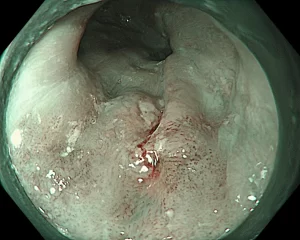

Khi sử dụng NBI, bác sĩ phát hiện một tổn thương phẳng, bắt màu nâu, kích thước khoảng 15mm. Tiếp đó, bác sĩ sử dụng hệ thống Olympus X1 và dây soi EZ1500 (độ phóng đại lên đến 150 lần) cho phép quan sát rõ vi mạch bề mặt.

“Đánh giá vòng mạch nhú nội biểu mô (IPCL) cho thấy đây là type B1 theo phân loại JES, gợi ý ung thư biểu mô vảy thực quản giai đoạn sớm ở lớp niêm mạc, có chỉ định điều trị bằng cắt tách dưới niêm mạc qua nội soi (ESD).

Tổn thương thực quản của bệnh nhân được nhuộm màu, phóng đại rất dễ quan sát (Ảnh: Bệnh viện cung cấp).